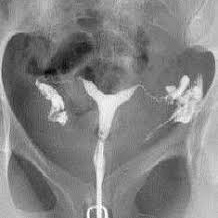

Histerosalpingografia. 877901 Idime (2022)

IDIME. Instituto de Diagnóstico Médico. Código de Convenio : 8915

BOGOTÁ

Sede Norte: Autopista Norte No. 122 – 68

BUCARAMANGA

Carrera 27 No. 30 - 15 Segundo Piso Hospital Universitario Los Comuneros

CALI

Calle 5 d # 38 A 35, Torre 1 Sotano 1

INCLUYE MEDIO DE CONTRASTE